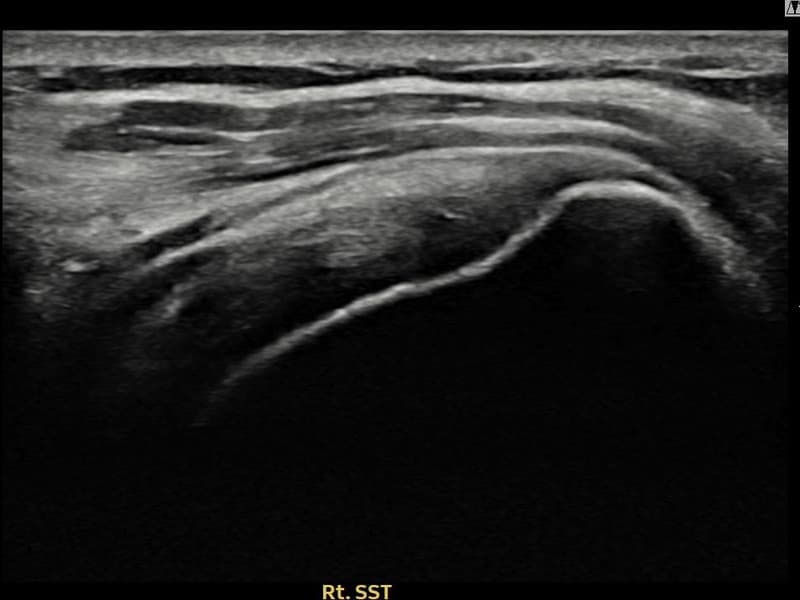

术前

术前超声确认右侧 冈上肌腱 关节面侧部分撕裂,右侧冈上肌腱回声不连续伴肌腱缺损(10mm × 4mm (肌腱厚度约40%缺损))。术后超声显示撕裂部位充满再生组织,肌腱连续性恢复,回声模式正常化。